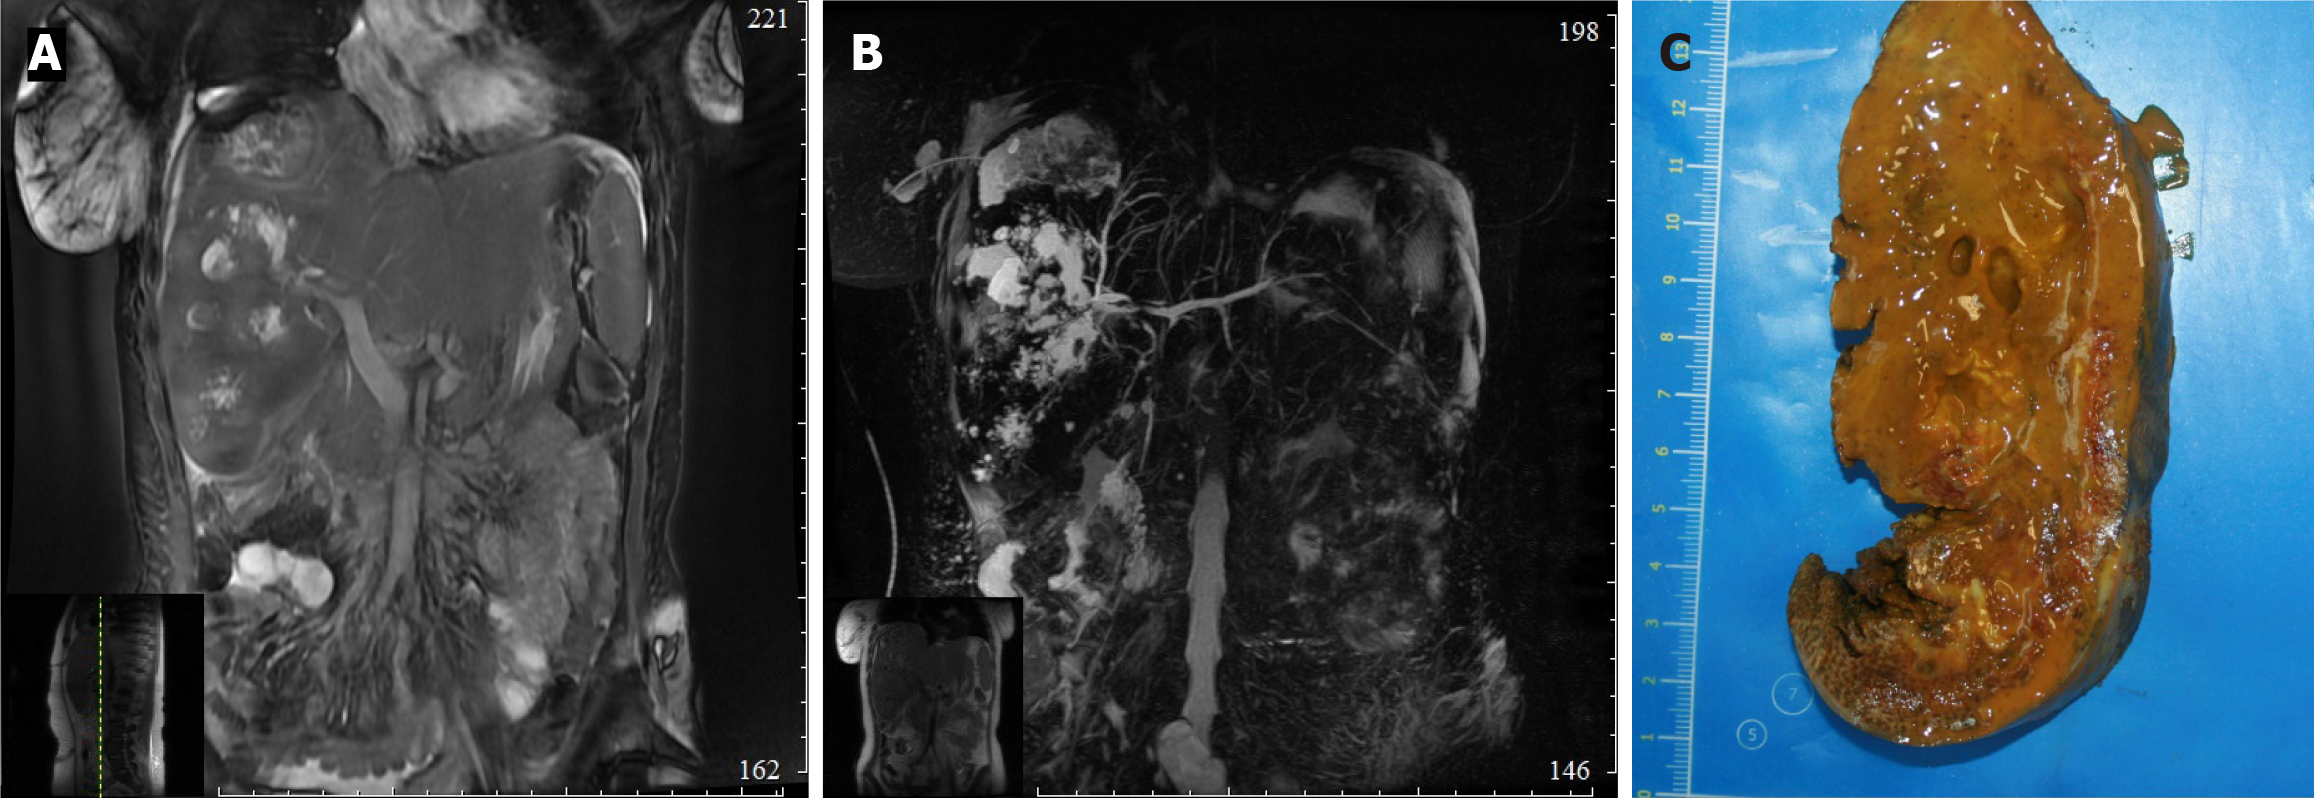

In one patient reconstructive surgery was refused due to severe somatic pathology, therefore combined (external and external-internal) PTBD was performed. Due to stenosis extending to intrahepatic bile ducts, 14 patients underwent hepatojejunostomy combined with liver resection of different volume (right-sided hepatectomy 4, left-sided hepatectomy 3, anatomical resection of II, III liver segments 7). Two out of 14 patients who underwent liver resection had previously diagnosed hepatic artery injury (Figure 2).